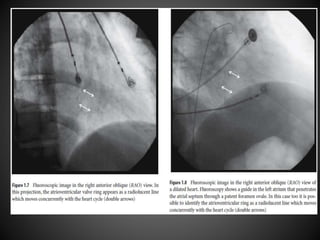

RAO view

Anatomy of RA - RAO view

Anatomy of RA- RAO view